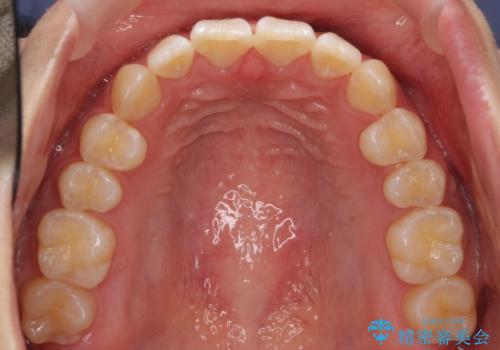

出っ歯 軽度のがたつき インビザラインで

- 20代女性

- インビザライン

- 3年1ヶ月

前歯のずれも治り、しっかり下がりました。

前歯を下げるのに、顎間ゴムを使用していただいています。